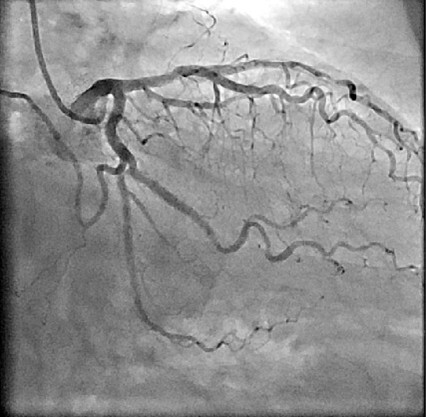

- 心臓カテーテル検査:手首や足の付け根に局所麻酔を行い、カテーテルという細いチューブを動脈の中に挿入し、透視下に冠動脈を直接造影する検査です。病気の程度を正確に診断し、適切な治療法を決定するのに有用な検査です。入院して検査を行います。所要時間は30分程度です。

(写真は心臓カテーテル検査によって得られた画像)